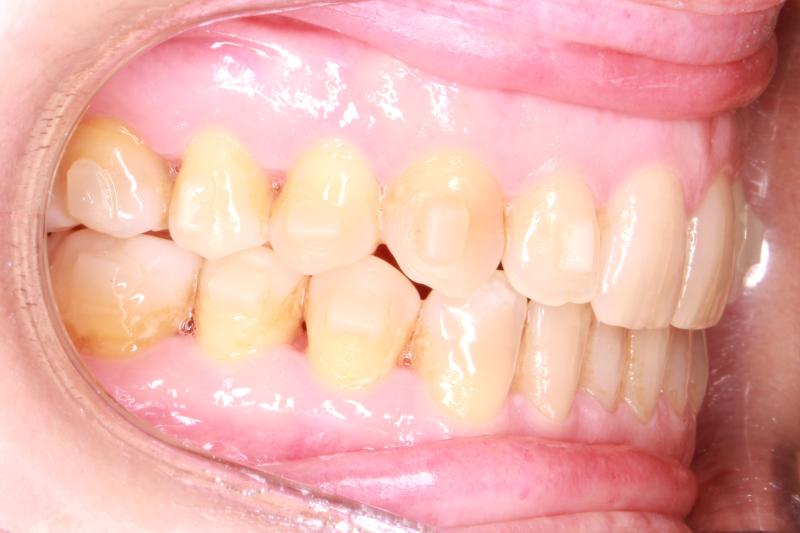

This article describes a treatment with spark aligners performed in a 52-year-old patient, who presented at the time of consultation with an increased overbite, moderate crowding in both arches, gingival smile and a clear alteration in the color of the enamel due to environmental factors.